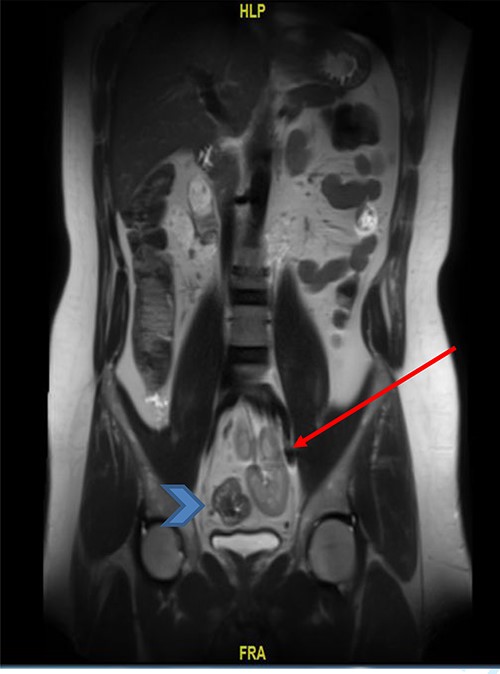

The basic lab Investigation showed Hgb level of 8.6 g/dL and CEA level of 4.8 ng/ml. On further investigation, colonoscopy revealed a large friable fungating circumferential rectal mass at 9 cm from anal verge extending to the distal sigmoid colon, it was nonobstructing with a length of 8 cm and the rest of the colon was normal. A biopsy from the mass was taken and showed invasive moderately differentiated adenocarcinoma. On further routine of radiological staging, CT of the chest, abdomen and pelvis confirmed the upper rectal mass with ectopic malrotated left kidney located in the lower abdomen and upper pelvis, opposite to L5-S1 vertebral bodies (Figs 1 and 2). There was no peritoneal disease or distant metastasis. Moreover, MRI pelvis showed again an upper rectal mass with mesorectal fat invasion and multiple lymph nodes (T3N2) and confirmed an ectopic left kidney (Figs 3 and 4).

MRI pelvis (coronal view) showed upper rectal mass with mesorectal fat involvement (arrowhead) and ectopic pelvic kidney (arrow).